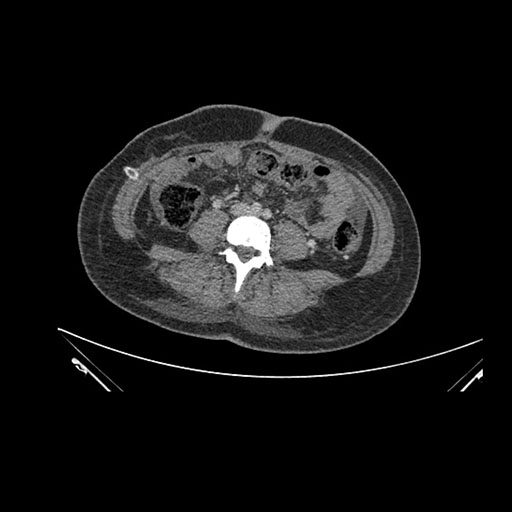

Imaging Analysis

Look through the patient's CT scan to identify any areas of concern for the necessary procedure.

Axial Arterial

Based on initial findings, which issue(s) would you be most concerned about?